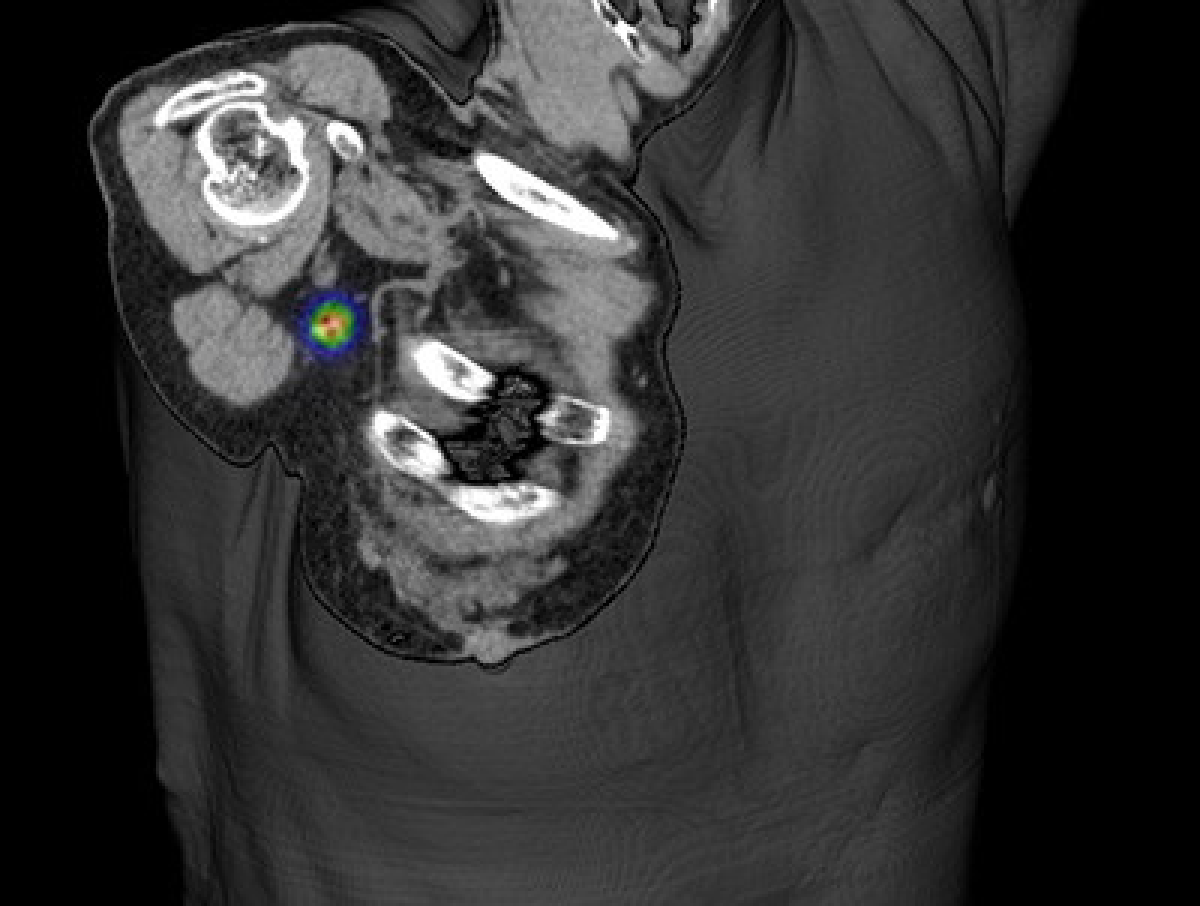

核医学

【センチネルリンパ節シンチグラフィ】

全身の各臓器やさまざまな腫瘍性疾患を対象に脳血流シンチグラフィや心筋血流シンチグラフィ、炎症シンチグラフィ、腫瘍シンチグラフィ、センチネルリンパ節シンチグラフィなどを行っています。

疾患に応じてSPECT/CT装置を用いて撮影しています。